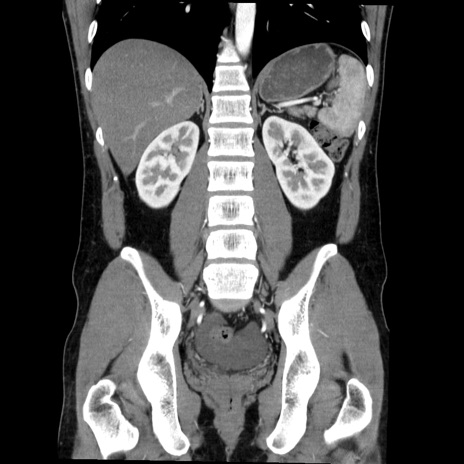

症例36(冠状断像)

【症例】20歳代 男性

【主訴】心窩部痛

【現病歴】今朝より上腹部痛あり。一旦軽快していたが再度出現したため救急要請。昨日夕に白身の魚を含む刺身を食べた。

【身体所見】BP 136/89mmHg、HR 74/min、BT 37.0℃、腹部:膨満、軟、心窩部に圧痛あり。反跳痛なし、筋性防御なし、腸雑音やや亢進あり。

【データ】WBC 17700、CRP 0.48